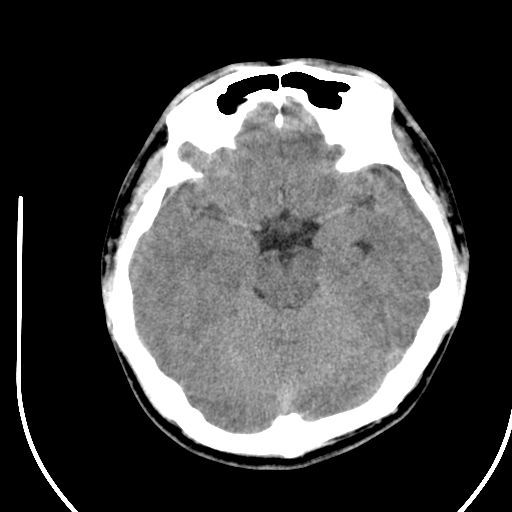

标题: CT28158:男,27Y。头痛数月,左顶叶血管瘤。 [打印本页]

标题: CT28158:男,27Y。头痛数月,左顶叶血管瘤。

海绵状血管瘤

考虑左顶叶海绵状血管瘤,建议mr检查。

左侧额叶海绵状血管瘤可能性大;建议行mri检查。

考虑血管畸形,因其周可见水肿,不除外感染性病灶。建议mri检查。